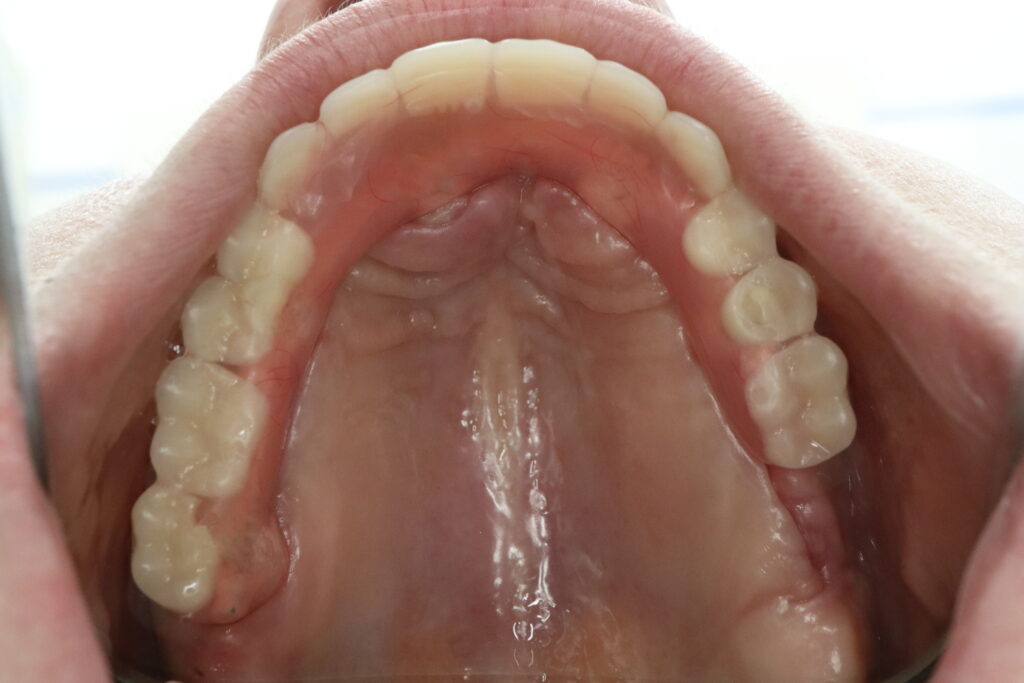

Ситуация до лечения

Диагноз: Полная адентия верхней челюсти и частичная вторичная адентия нижней челюсти.

пациент до имплантации